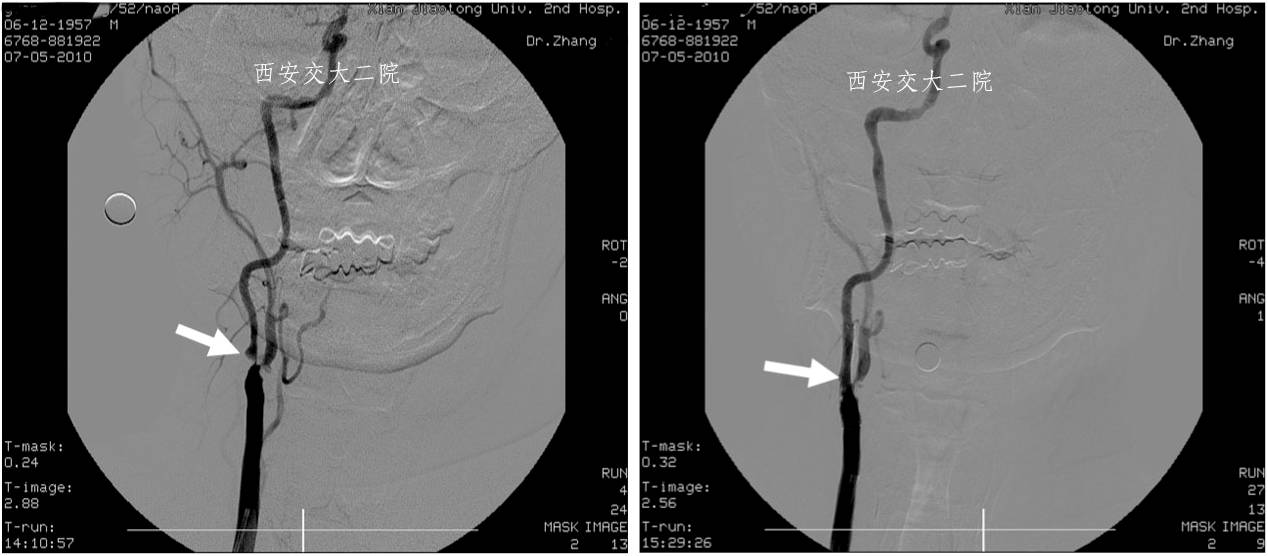

Case 1 颈内动脉C1段急性闭塞(2009年)

》男,70岁,突发右侧肢体无力3小时,DSA提示左侧颈内动脉起始段闭塞。

Case 1 颈内动脉狭窄支架成形术(2009年)

》男,52岁,发作性左侧肢体无力2周,右ICA开口狭窄支架后。